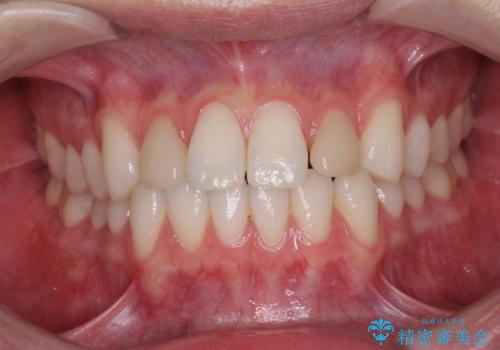

- 前歯のラミネートベニアの不自然な色合いを気にして来院された患者様です。

ホワイトニングを併用し、治療前と比べて自然でとても明るい口元となりました。